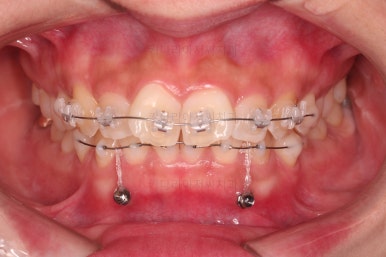

과개교합 개선을 위해서 미니스크류까지 힘을 줘서 아래 앞니를 내려줍니다.

장치 부착 시점의 장치가 보이는 모습과 입매 변화 관찰해 주시고요.

중간중간 미니스크류가 빠지든, 위치적으로 좋은 곳을 선택하든 여러 이유로 미니스크류 재식립이 몇 번 있었고요.

디테일을 위해서 윗니는 어금니에도 하나씩 장치를 더 부착했고, 아랫니는 바로 뒷 치아에도 장치를 부착했습니다.

과개교합 개선에 미니스크류까지 사용되었던 터라 매우 난이도가 높은(전체교정보다 훨씬 난이도가 높습니다.) 부산앞니부분교정이어서 1년여의 기간이 걸렸는데요.

기왕(부분교정임을 감안했을 때) 오래 걸린거 좀 더 완성도를 높이고자 아래 앞니는 설측교정까지 부착했습니다.

역시 미니튜브 장치를 이용했고, 아래 앞니 안쪽에다가 장치를 부착해서 아주 미세한 배열을 맞춰드렸습니다.